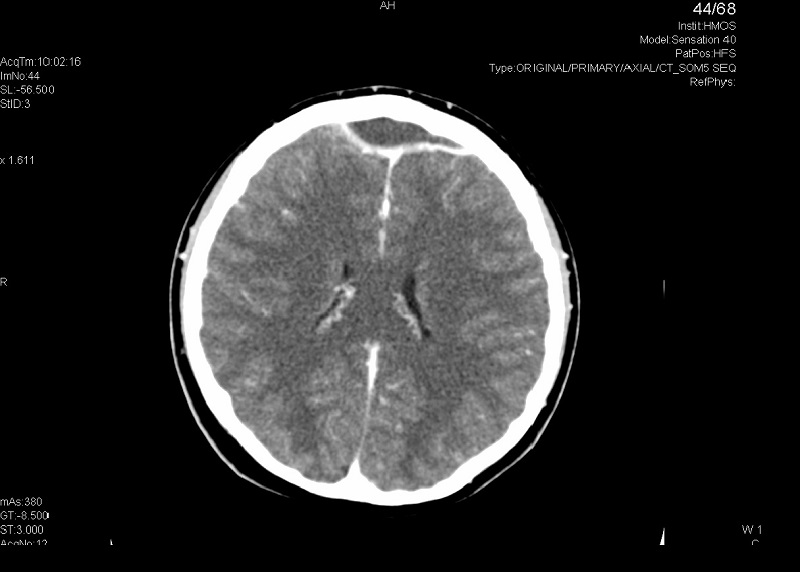

Ante los hallazgos del fondo de ojo se decide realizar una tomografía computarizada (TC) craneal, que es compatible con sinusitis en senos paranasales izquierdos frontal, maxilar y celdillas etmoidales anteriores-medias complicada con absceso epidural anterior bifrontal (de 6 × 2 cm) y solución de continuidad/dehiscencia milimétrica en pared posterior de seno frontal izquierdo.

Tras 2 semanas de evolución de la sinusitis, el fondo de ojo y la prueba de imagen (TC craneal) fueron claves para llegar al diagnóstico.